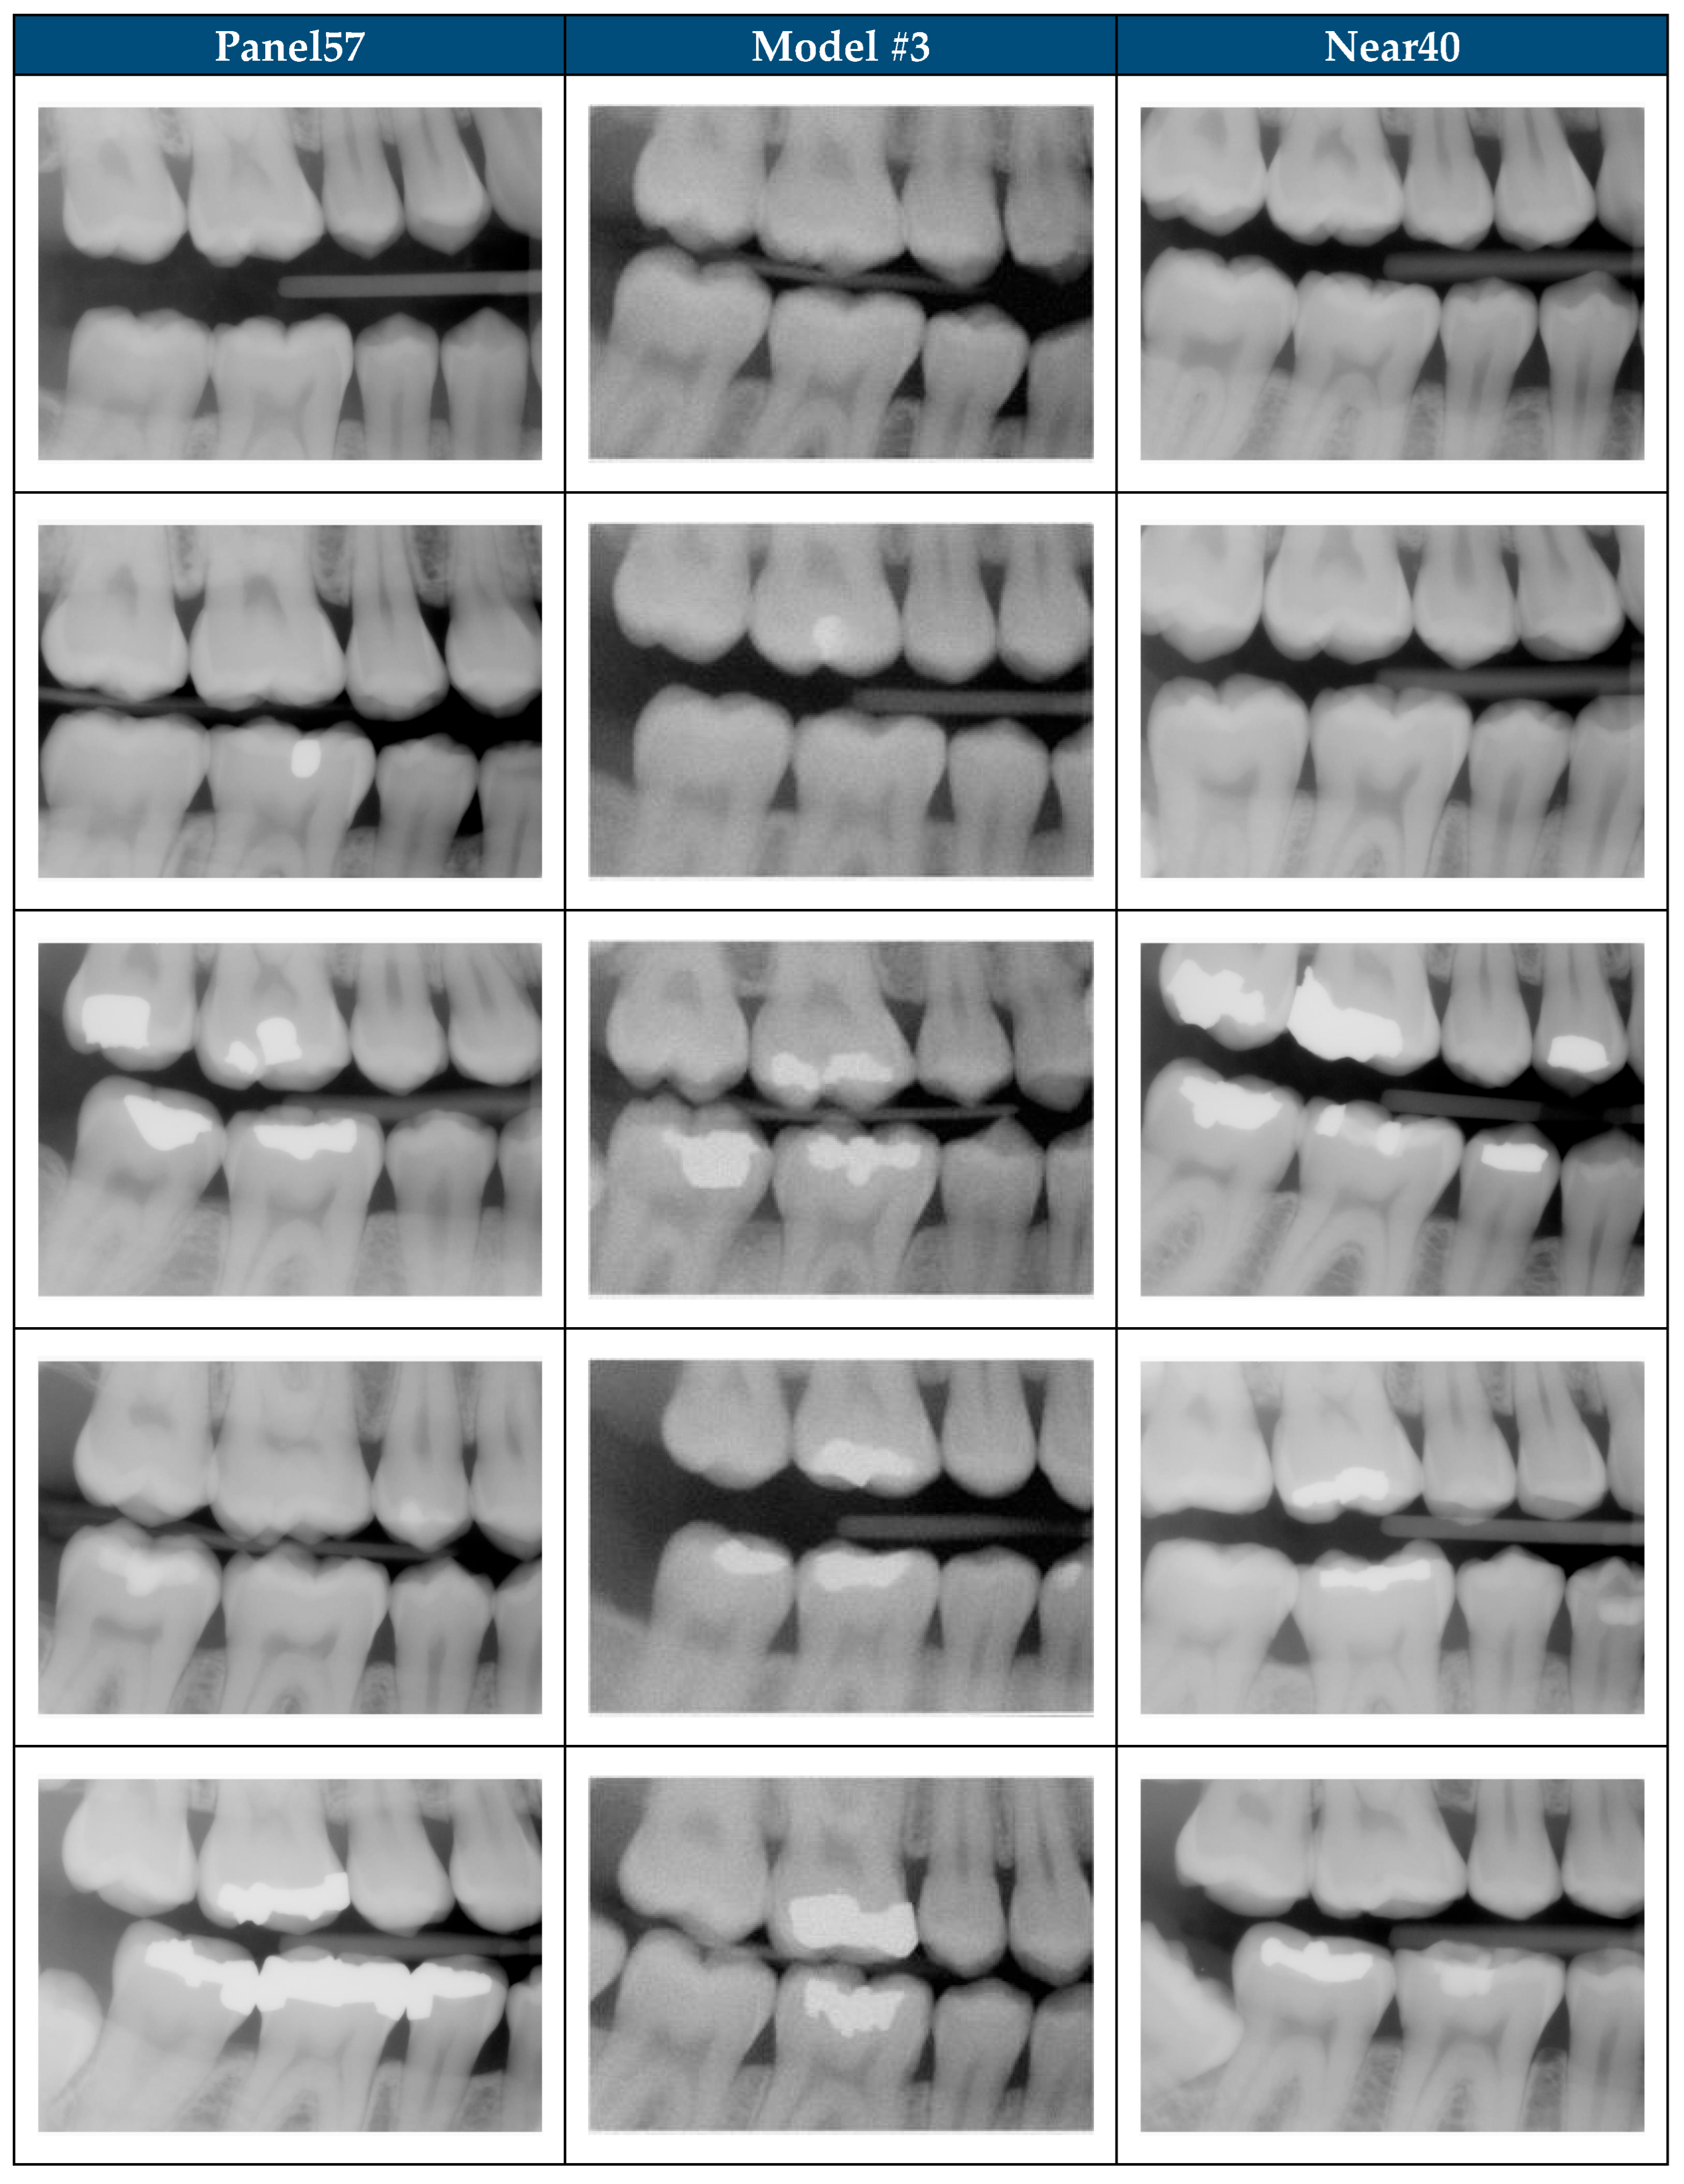

| Category | Description | Sample Images | |

| 1 | The image appears to be a realistic dental radiograph representative of the training data. (Looks real with no anatomic anomalies) | ![]() | ![]() |

| 2 | Image resembles a realistic dental radiograph representative of the training data but contains anatomical hallucinations or abnormalities. (Looks real but tooth count, order or anatomy is unreal) | ![]() | ![]() |

| 3 | Image is unrealistic but resembles the general appearance of dental radiograph represented in the training data. (Looks like a dental radiograph with features that are obviously fake) | ![]() | ![]() |

| 4 | The image is unrealistic, but portions of the image contain dental-related attributes. (At minimum portions of tooth anatomy are present) | ![]() | ![]() |

| 5 | No recognizable dental-related attributes. | ![]() | ![]() |